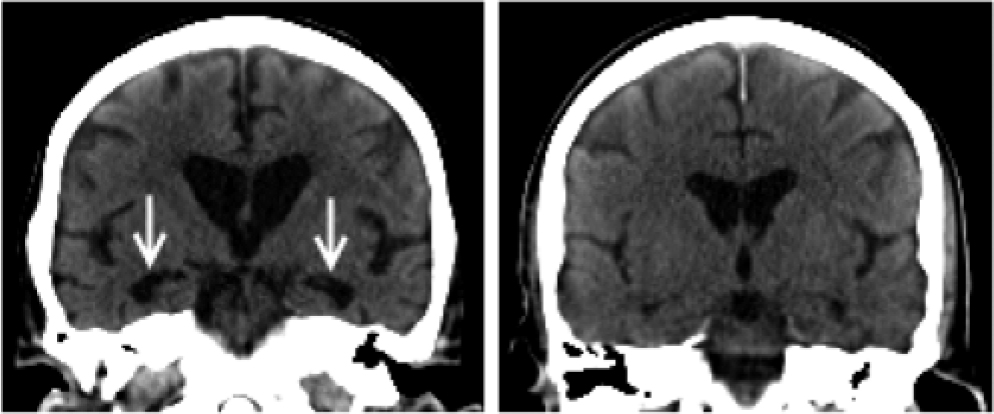

Computed tomography

All CT scans were reconstructed as 3 mm thick coronal sections oriented perpendicular to the long axis of the hippocampus by the same operator. Visual rating was performed with a standardised scale (Scheltens scale) to rate right and left MTLA separately. Reference Scheltens, Leys, Barkhof, Huglo, Weinstein and Vermersch6 The scale rates atrophy on a 5-point scale (0 = absent, 1 = minimal, 2 = mild, 3 = moderate and 4 = severe) based on the height of the hippocampal formation and the width of the cerebrospinal fluid (CSF) spaces. For the purpose of analysis, the left and right scores were summed to give a combined MTLA score (maximum score 8). All scans were assessed by consensus between two experienced raters (SC and RB) blinded to diagnosis. Figure 1 shows example CT scans.

Fig. 1 Computed tomography of dementia with Lewy bodies with (left) high and (right) low medial temporal lobe atrophy (MTLA): MTLA = 8 v. MTLA = 2, respectively. Greater medial temporal atrophy (arrowed) is clearly visible in the left-hand scan.

Figure 1 shows typical CT scans, and Fig. 2 shows the MTLA rating scores by group. In our previous examination of MTLA, we found that a cut-off of ⩾5 optimally distinguished Alzheimer's disease from DLB and vascular dementia. Reference Burton, Barber, Mukaetova-Ladinska, Robson, Perry and Jaros7 With this cut-off, none of the control participants, 6/30 DLB, and 23/37 Alzheimer's disease, had marked MTLA. So a high MTLA score was a good test for excluding non-dementia and most DLB cases, with a positive predictive value of 79%, but a lower sensitivity (62%) for detecting all Alzheimer's disease cases.